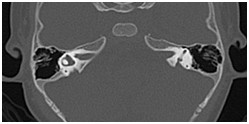

影像科在五官疾病诊治中的严谨、专业,全面开展眼、耳、鼻、喉精细化检查及诊断。

鼻窦(病例-异物):

颞骨及耳(病例-前庭导水管扩大)

眼眶(病例-眼上静脉扩张)